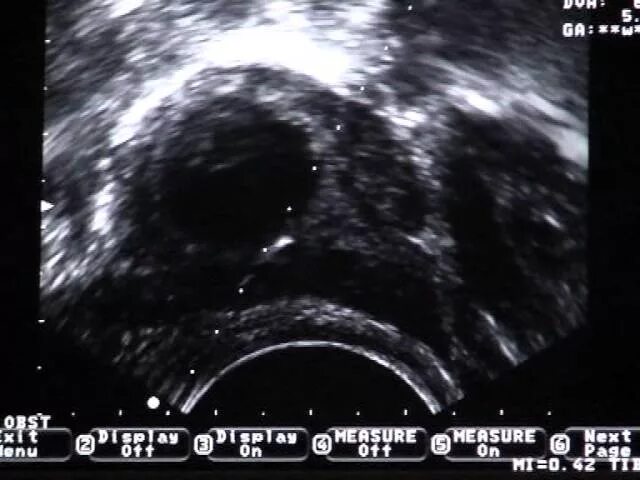

Почему неудачное эко